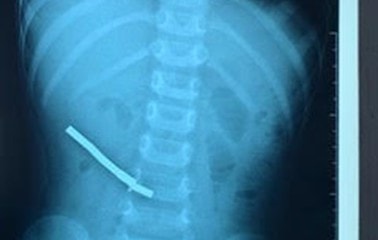

Nuốt 27 cục nam châm, bé gái 2 tuổi bị thủng đường tiêu hóa nhiều chỗ

Bé gái 2 tuổi bị thủng đường tiêu hóa nhiều vị trí do nuốt 27 cục nam châm đã được bệnh viện Nhi đồng Đồng Nai cấp cứu thành công.

Đau bụng, bé 3 tuổi ở TPHCM đi khám phát hiện thủng nhiều đoạn ruột vì nuốt 31 viên nam châm đồ chơi

Quá trình phẫu thuật nội soi ổ bụng, bác sĩ ghi nhận ruột thủng nhiều nơi, ổ bụng nhiều phân, giả mạc, tách dính ruột, ghi nhận nhiều viên nam châm (giống hạt cườm) dính nhau.

Sáng 8/2: Nhiều tỉnh, thành tiêm vaccine COVID-19 thấp; Trẻ 2,5 tuổi nuốt 14 viên nam châm gây thủng tắc ruột

Theo thống kê của Bộ Y tế, hiện tròn 38 ngày Việt Nam không ghi nhận ca tử vong do COVID-19; Đến nay nước ta đã tiêm hơn 266,2 triệu liều vaccine COVID-19, tuy nhiên vẫn còn nhiều tỉnh, thành phố tiêm vaccine chậm, thấp; Cứu sống trẻ 2,5 tuổi nuốt 14 viên nam châm gây thủng tắc ruột.

Gắp dị vật nam châm ở tá tràng cho bé trai 18 tháng tuổi

PLBĐ - Sau khi được các bác sĩ thăm khám và chụp X-quang, xác định có hình ảnh dị vật cản quang nằm trong tá tràng, bệnh nhi được chuyển đến Trung tâm Nội soi để tiến hành nội soi cấp cứu, gắp dị vật là nam châm kích thước 6x6mm tại tá tràng D2 ra ngoài.

Chơi bi nam châm thông minh đang "gây sốt", bé trai 6 tuổi thủng dạ dày

Những viên bi nam châm "xếp hình thông minh", món đồ chơi đang gây sốt đã khiến cậu bé 6 tuổi nhập viện trong tình trạng dạ dày, hồi tràng bị thủng.

Bé trai phải cắt bỏ 20 cm ruột do nuốt 6 thỏi nam châm, 3 kim bấm

Bệnh viện Nhi Đồng 1 vừa phẫu thuật cấp cứu lấy dị vật là 6 thỏi nam châm cùng 3 kim bấm và phải cắt bỏ 20 cm ruột cho bé trai 3 tuổi.

Lấy 8 thanh nam châm trong bụng bé trai 4 tuổi

Các bác sĩ tại Bệnh viện Nhi Đồng 2 phẫu thuật cấp cứu bé trai 4 tuổi thủng ruột do nuốt 8 thanh nam châm.